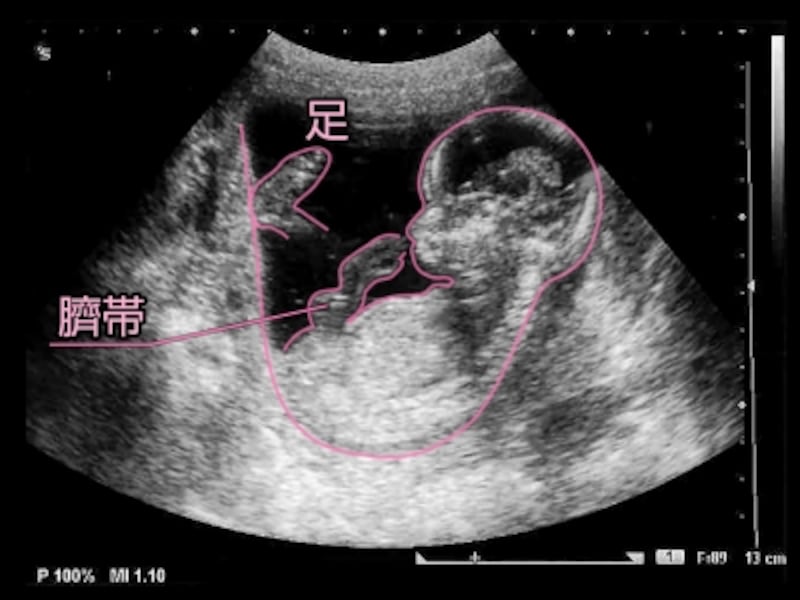

エコー写真 性別の見分け方 男の子女の子別エコー 妊娠週まとめてみました ママびよりウェブ

エコー写真を妊娠の経過別に紹介 見方や性別の見分け方

エコー写真を妊娠の経過別に紹介 見方や性別の見分け方

エコー写真 性別の見分け方 男の子女の子別エコー 妊娠週まとめてみました ママびよりウェブ

エコー写真 性別の見分け方 男の子女の子別エコー 妊娠週まとめてみました ママびよりウェブ

エコー写真 性別の見分け方 男の子女の子別エコー 妊娠週まとめてみました ママびよりウェブ

エコー写真 性別の見分け方 男の子女の子別エコー 妊娠週まとめてみました ママびよりウェブ